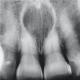

: QUISTE NASOPALATINO